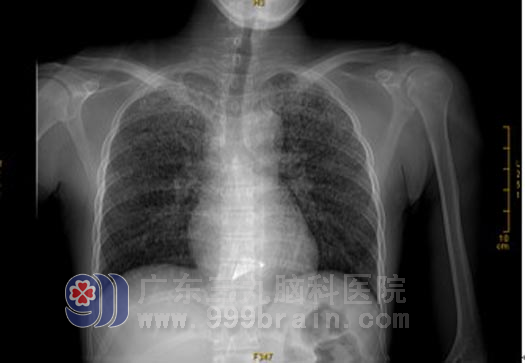

胸部X光片示急性血行播散型肺结核